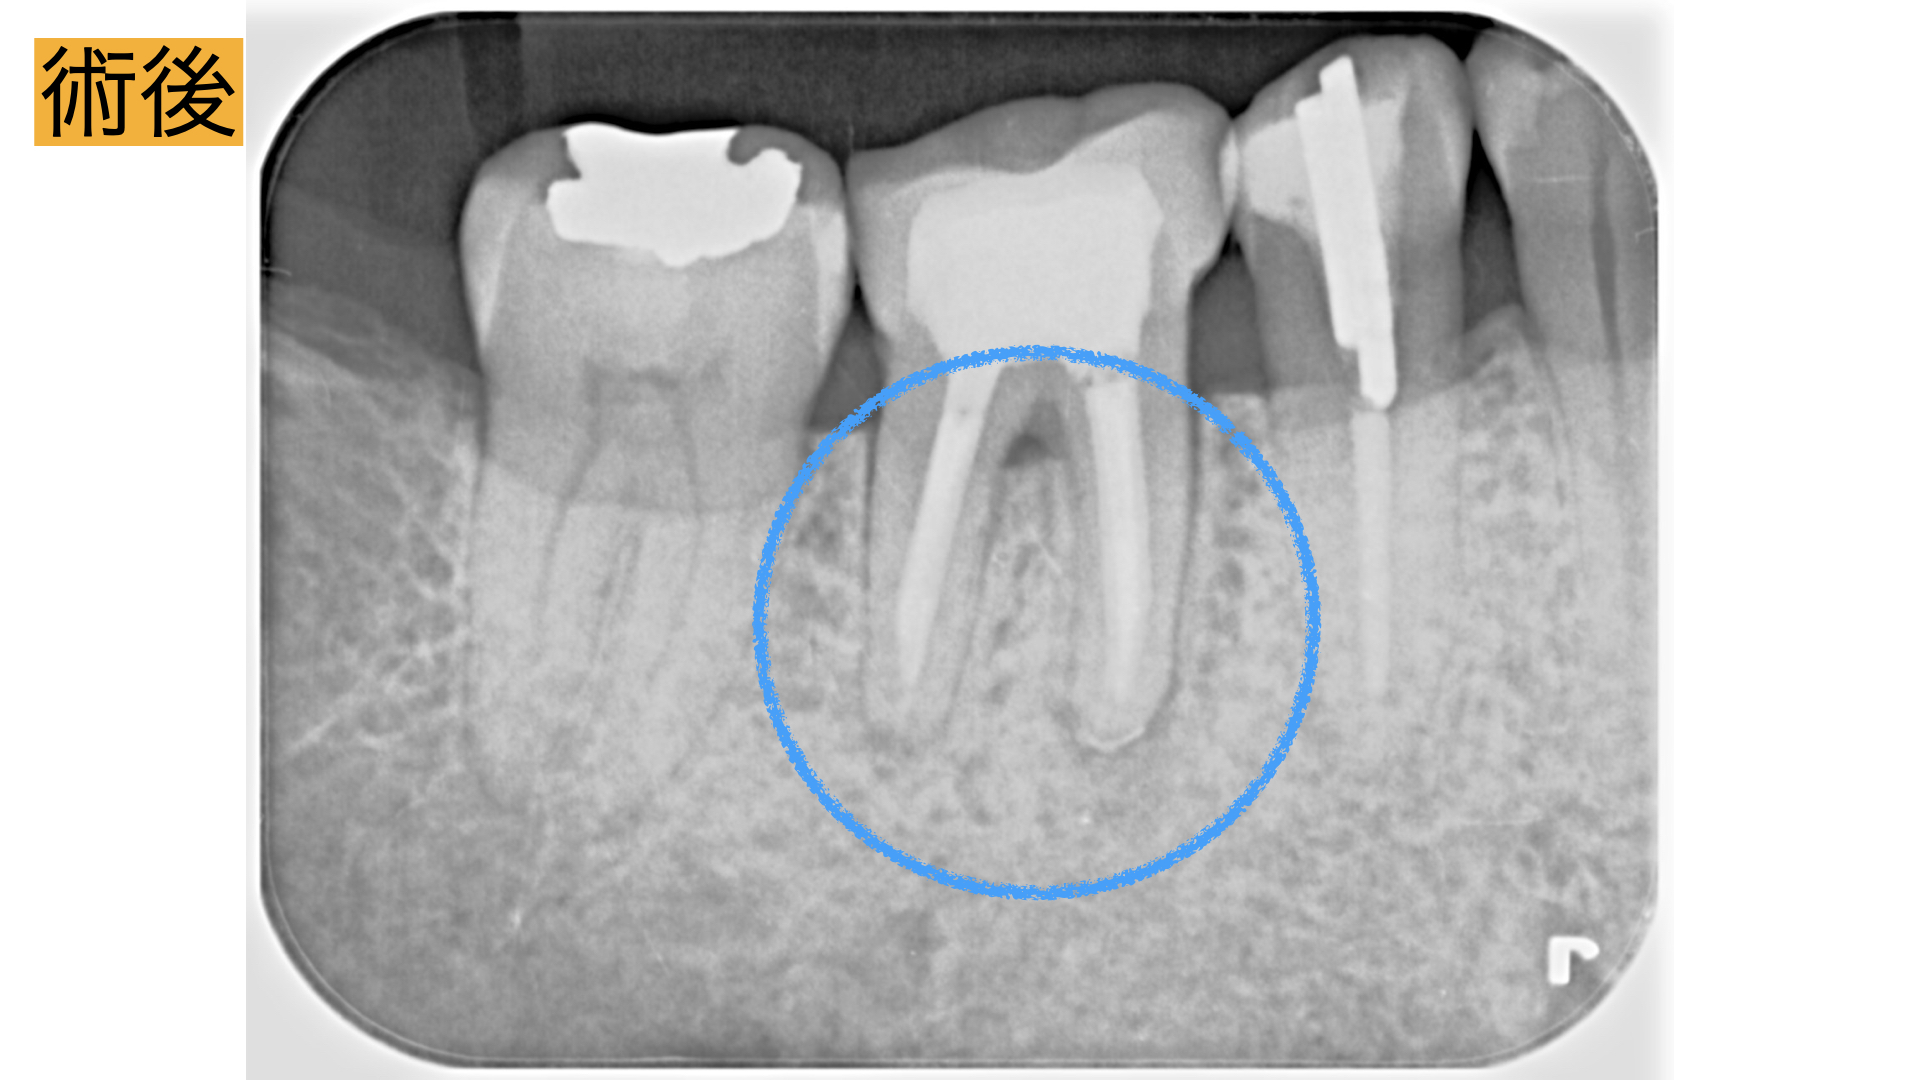

術後

術直後から痛み、腫れは、解消し2年間の経過観察も問題なく過ごせましたとのことでした。 レントゲンで骨の回復が確認とれ、非常に驚かれておりました。